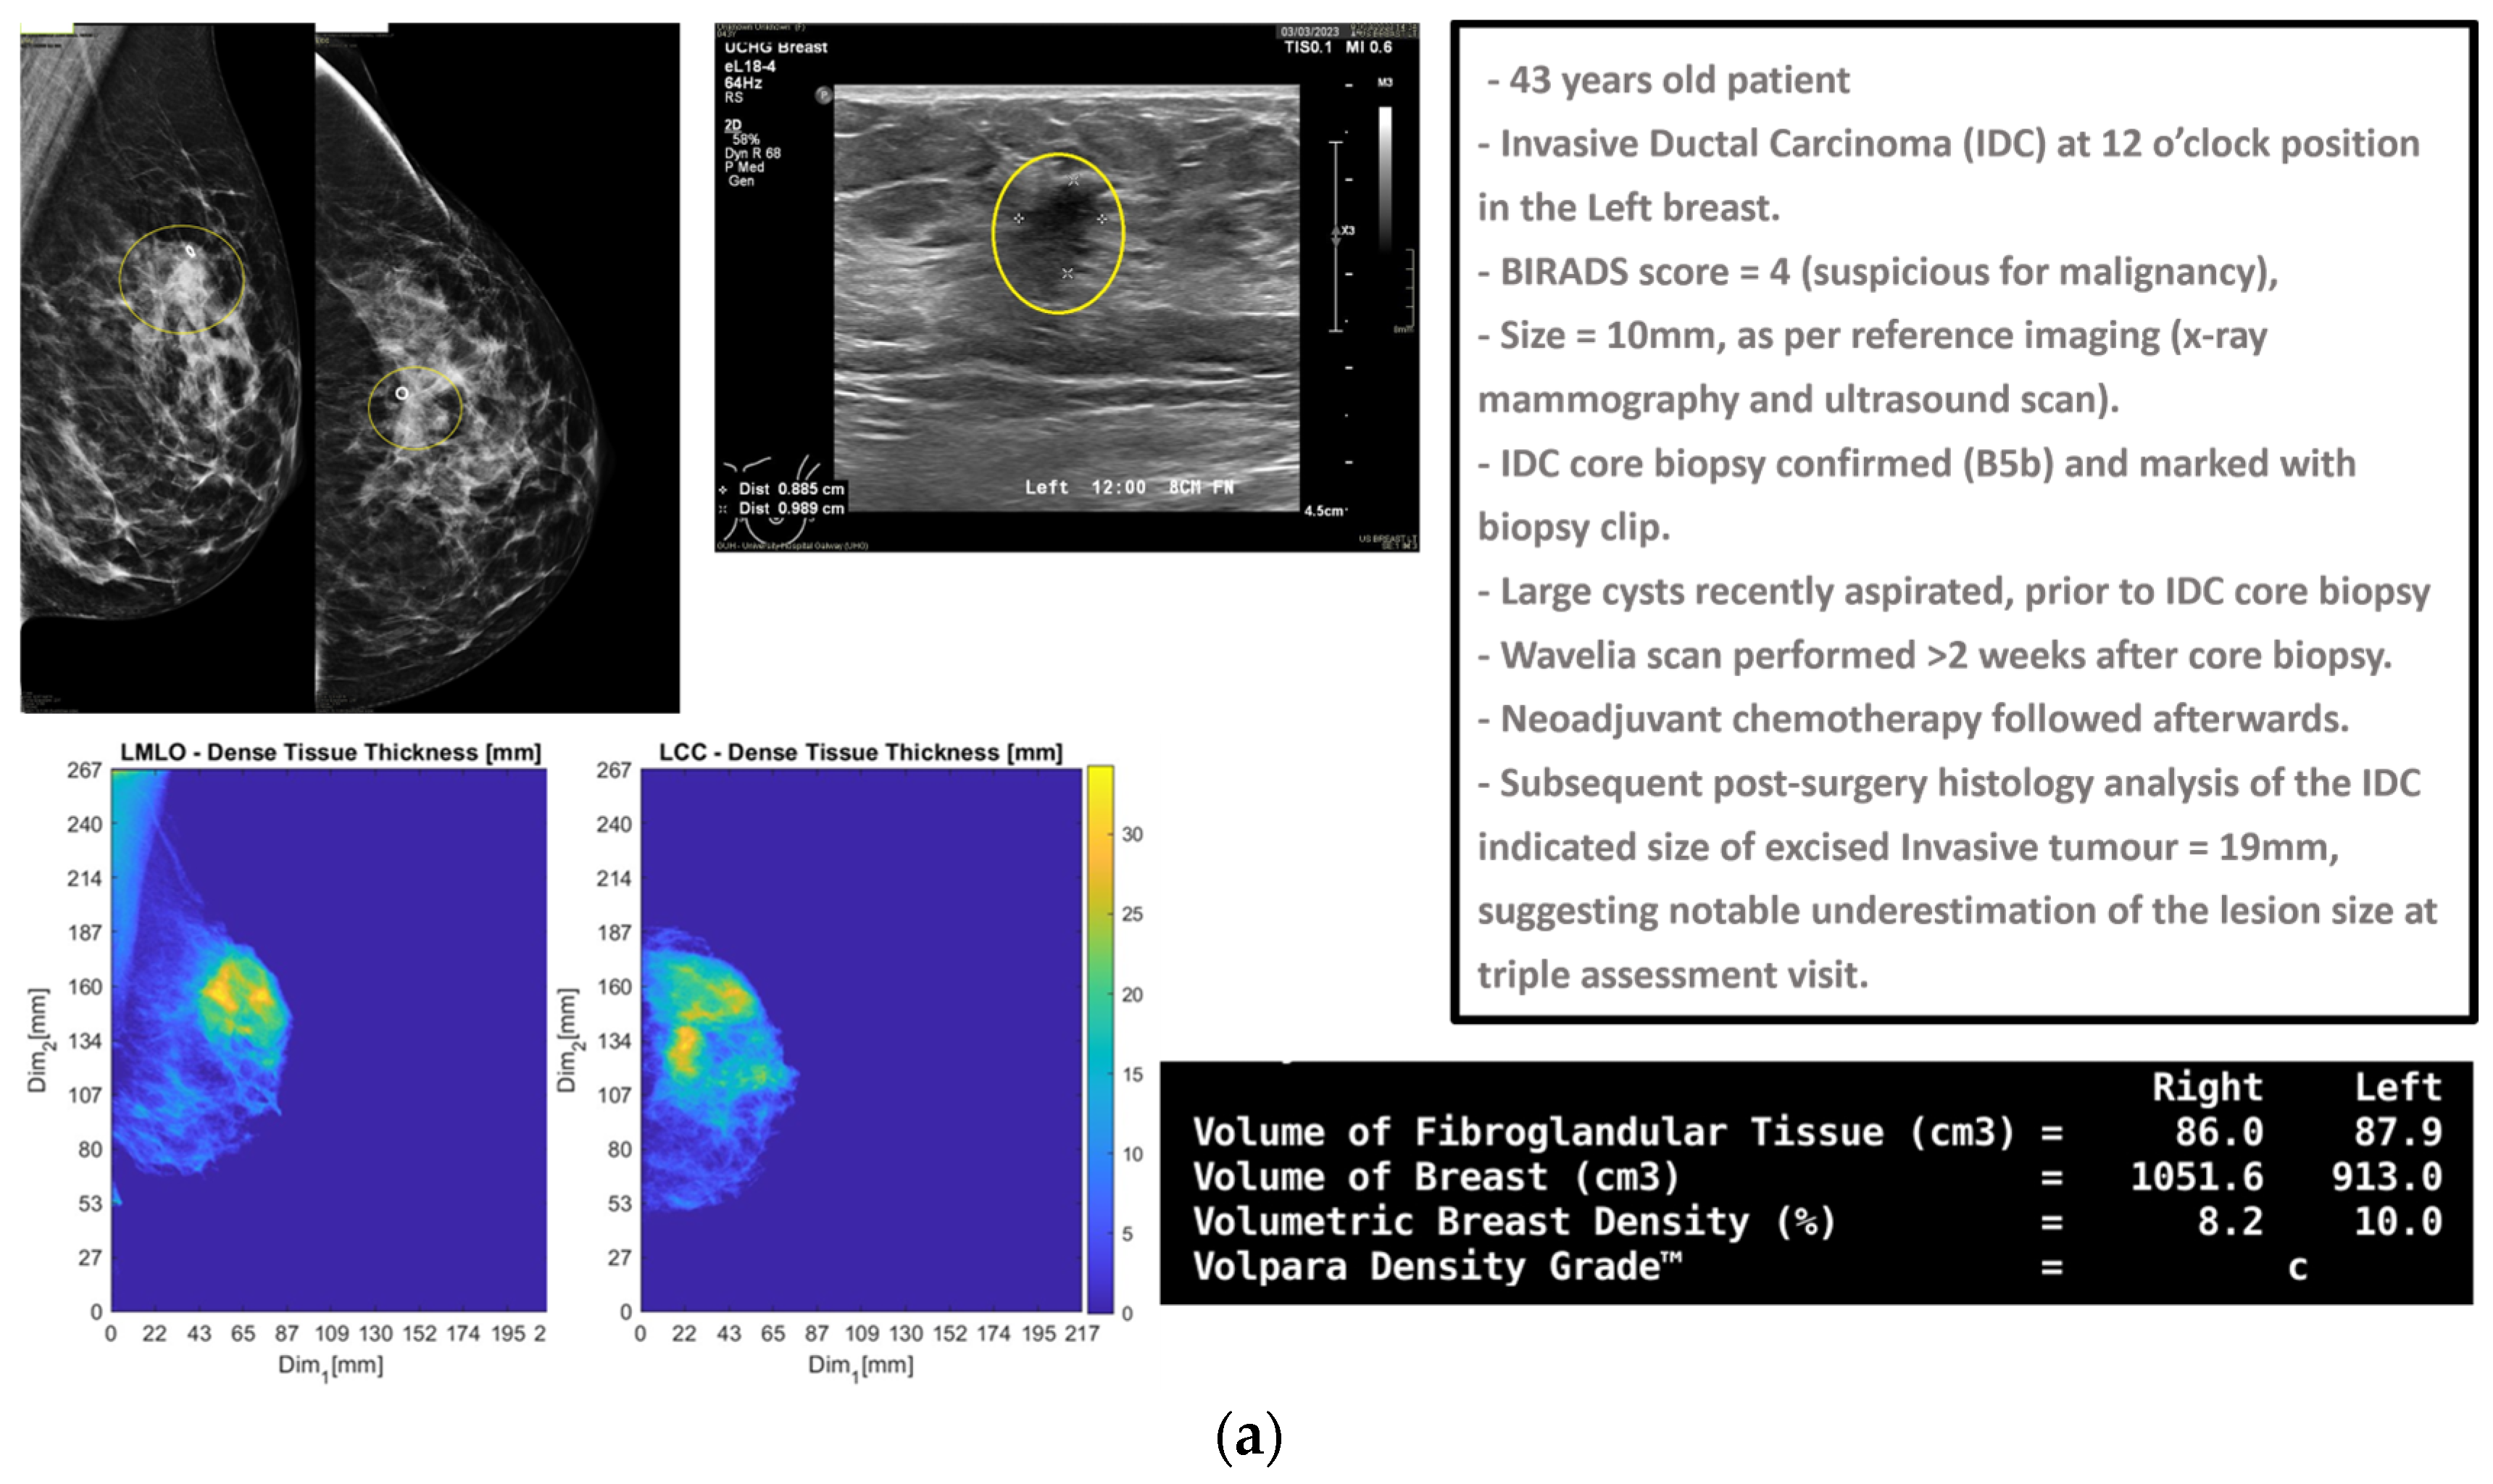

3.2. Typical Malignant and Benign Lesions: MWBI Images and Extracted Lesion Features

In this section, the characteristics of four typical cases of breast lesions (two malignant and two benign) with good-quality MWBI scans, resulting in a clear representation of these lesions as malignant or benign in the Wavelia feature analysis space, are discussed.

The principal characteristics of these lesions and a representative subset of the features that were computed for the associated ROIs, as extracted from the MWBI images, are summarized in Table 2. The points that represent the four lesions on the scatter plot of an indicative three-dimensional representation of the Wavelia MWBI feature analysis space are highlighted and labeled in Figure 8.

An illustrative subset of the Wavelia MWBI imaging outputs, together with the ultrasound reference scan, is depicted in Figure 9 for each of the four cases. In Figure 9a, endoscopic camera views showing the position and orientation of the four breasts in the MWBI scanner are depicted.

A quite stable Signal-to-Noise Ratio (SNR) level, in conjunction with overall comparable Contrast-to-Noise Ratio (CNR) levels, slightly increased in the case of Patient 003 (IDC, molecular subtype Luminal A), is observed in Table 2 for the four cases. The SNR measures the ratio of the mean signal intensity within the ROI to the standard deviation of the background noise. A higher SNR generally indicates a better image quality. The CNR measures the difference between the mean ROI intensity and the mean background intensity, relative to the background noise. CNR quantifies how well the ROI stands out from its surroundings. An insightful comparison of these levels to the ones of the images in confusing cases of lesions, which are not clearly identifiable as malignant or benign on the Wavelia MWBI feature analysis space, is provided in the following section.

Good correspondence between the morphology and maximal linear dimension of the extracted ROIs from the Wavelia MWBI volumetric images and the ultrasound reference representations of the lesions is notable by comparative visual inspection of the images in Figure 9c–e. The case in Figure 9b is the same case used in Section 2 to illustrate the layout of the Wavelia MWBI imaging and image analysis outputs in Figure 1 and Figure 2, respectively. Based on the more detailed clinical reference information provided for this case in Figure 1a, there is clear evidence that the ultrasound scan provided only partial visibility of this IDC, resulting in a severe underestimation of its size in this case. The 19 mm size of the excised tumor, as per the post-surgery histology report, also considering that the patient underwent neoadjuvant chemotherapy before surgery and after the Wavelia MWBI scan of the breast, renders the MWBI-based estimate of the lesion size relevant and worth highlighting in this case.